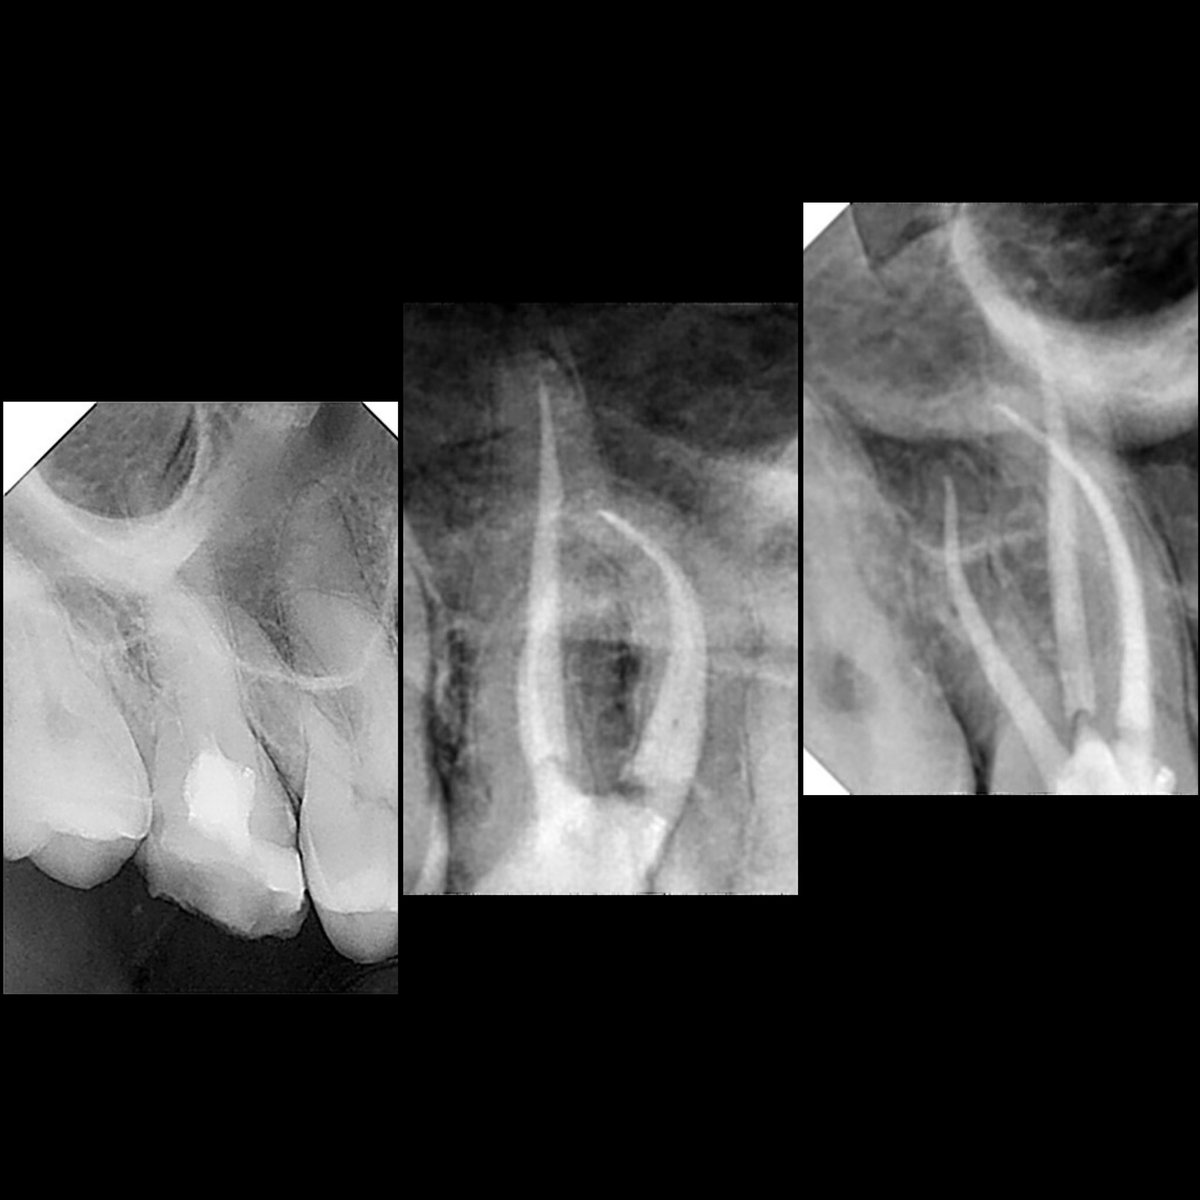

@ClaytonBigsbyEt الله يسلمك حياك الله ، في هالحاله الغالب - Torsional fatigue when the tip became locked in the canal while the remaining part continued to rotate around it.

@i_th44 ماشاء الله دكتور تسلم يدك ، بس سؤال دكتور ايش السبب اللي يخلي الفتيل ينكسر في هذي الحالة القناة مستقيمة تقريبا والفايل تقريبا ثلثه اللي مكسور ؟